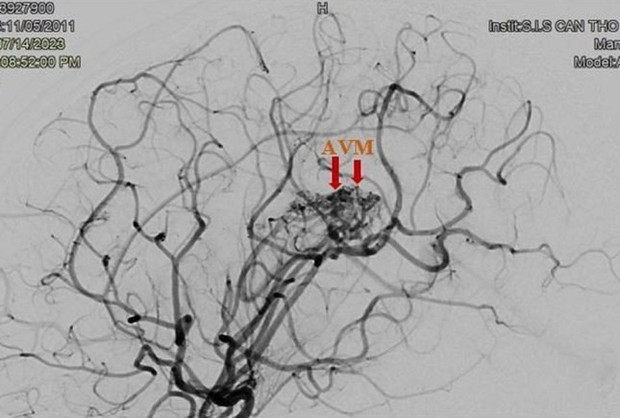

Túi giả phình mạch máu não của bệnh nhân trên hình ảnh kiểm tra

BS Ngô Minh Tuấn, Trưởng khoa Chẩn đoán Hình ảnh, Bệnh viện S.I.S Cần Thơ, cho biết, bệnh nhi đã bị xuất huyết não do vỡ dị dạng thông động tĩnh não AVM và có túi giả phình lớn (kích thước 3x3mm) trong búi dị dạng. Đây là tình trạng rất nguy hiểm, các bác sĩ đã tức tốc can thiệp xử lý vị trí mạch máu dị dạng bị vỡ và tắc túi giả phình giúp bệnh nhân qua nguy kịch.